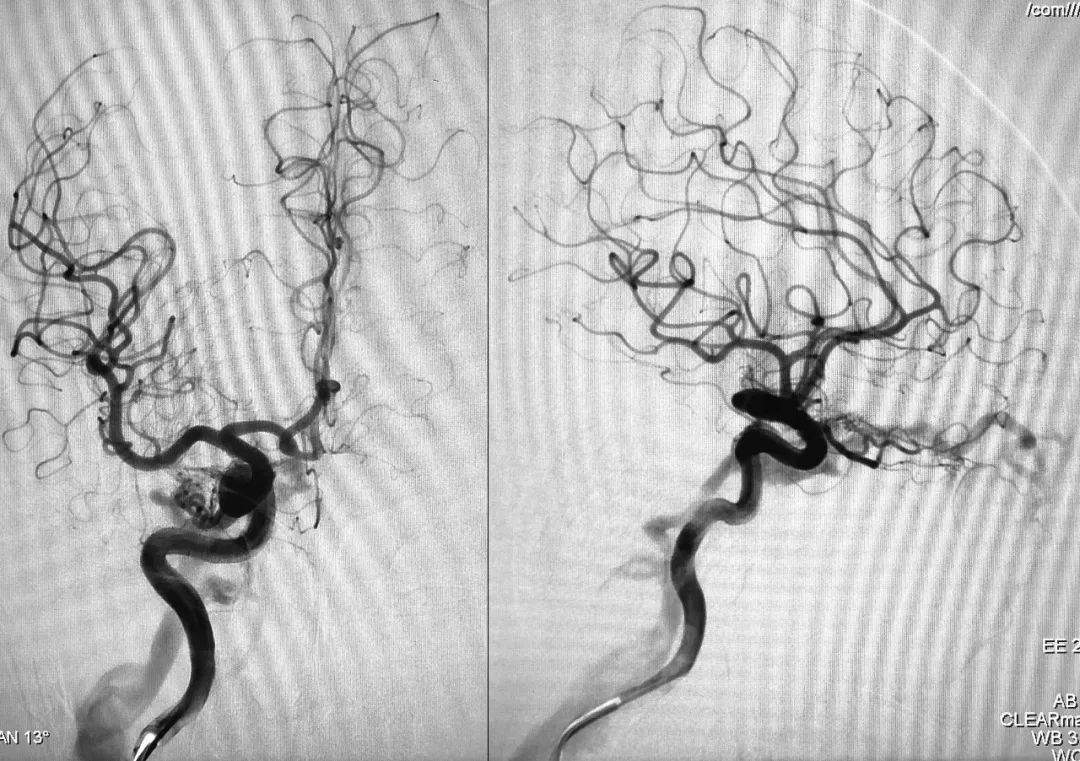

⑦ 术后左颈总动脉正、侧位造影显示瘘口不显影:

将造影管移入右侧颈总动脉,正、侧位造影显示瘘口不显影:

术后正、侧位蒙片显示伊维尔-Ⅰ胶在右侧海绵窦内的铸型(约6 ml):